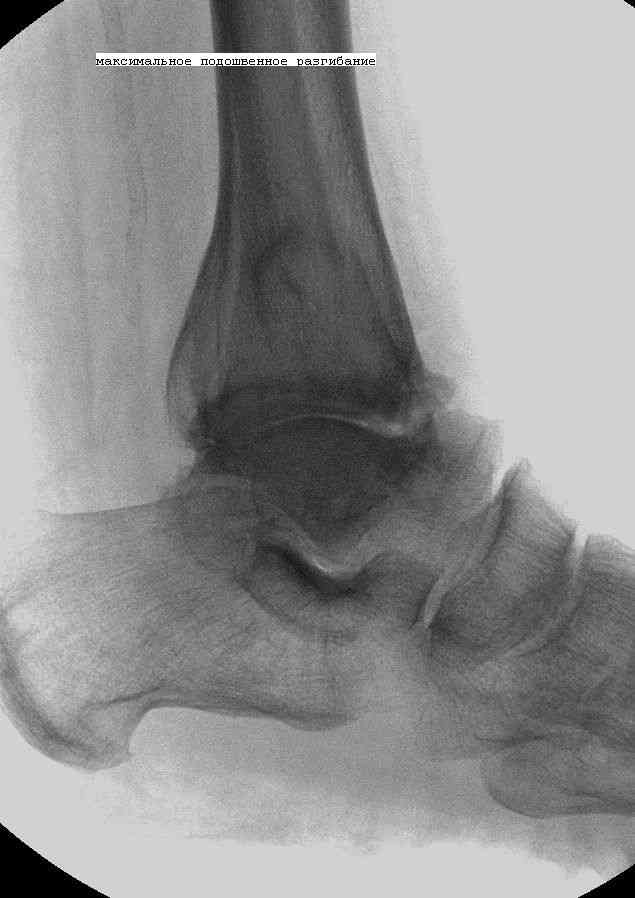

Эндопротезирование или артродезирование ?К нам обратился пациент 73 лет с жалобами на боли и деформацию в области левого голеностопного сустава. В анамнезе: в 1980 году перелом обеих лодыжек с вывихом стопы кнаружи. Лечился консервативно: одномоментная репозиция переломовывиха в левом голеностопном суставе с трансартикулярной фиксацией голеностопного сустава спицами Киршнера через пяточную, таранную, большеберцовую кости. Накладывалась гипсовая иммобилизация. Даная манипуляция осложнилась нагноением с развитием гнойного артрита. Были удалены спицы, сустав со слов больного, промывался растворами, но не вскрывался, получал антибиотики. Гнойный процесс был купирован, и рецидива с тех пор не было.Об-но: Левый голеностопный сустав деформирован за счет разрастания костной ткани и отечности мягких тканей. Левая стопа с вальгусной установкой, практически отсутствуют все своды левой стопы (стопа плоская). Полный объем движений в левом голеностопном суставе максимум достигает 15 гр, движения стопы в основном за счет подтарнного сустава. Пальпаторно область голеностопного сустава не столь болезненна, как болезненна область подтаранного сустава и область таранно-ладьевидного сустава.После изучения объективного статуса, анамнеза, рентгенснимков, больному предложен был трехсуставной артродез, так-как мы сочли это наиболее приемлемым в данном случае. Но больной отказывается от данной операции и настаивает на эндопротезировании левого голеностопного сустава. Во первых, наше отделение не имеет опыта в эндопротезиовании голеностопного сустава. Во вторых, нам кажется, что трехсуставное артродезирование в данном случае наиболее подходящее. Причиной тому, на наш взгляд, выраженная деформация левой таранной кости, как следствие аваскулярного некроза, и то что болит не голеностопный сустав в данном случае ( хотя в нем и ограничено движение), а подтранный и таранно-ладьевидный суставы и то что эндопротезирование одного голеностопного сустава не решит проблем в подтаранном, ладьевидно-таранном сочленениях. Наши доводы оказались безуспешными, а так как пациент является ученным, требовал доказательной базы наших умозаключений. Ваше мнение по данному случаю, и мы были бы благодарны, если у кого то есть материал по данной теме или есть ссылки. Заранее благодарны всем, кто примет участие в обсуждении данной темы.

По всем канонах хирургии стопы асептический некроз таранной кости - абсолютное противопоказание для эндопротезирования голеностопного сустава.